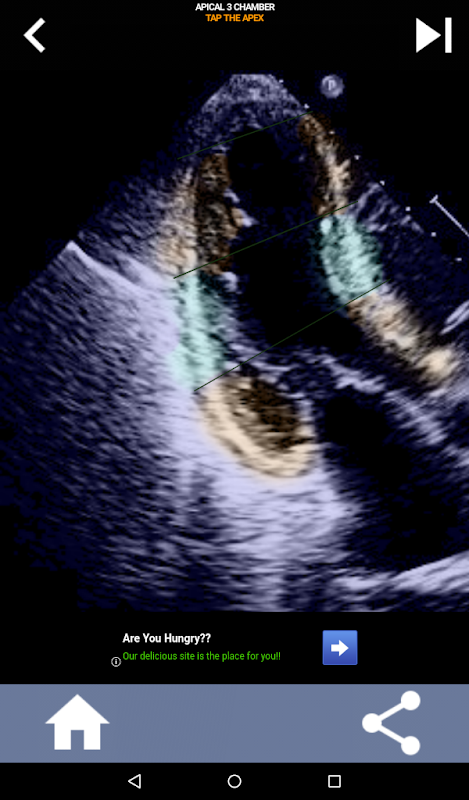

Quiz-based visual approach to learning the AHA heart segments: Echocardiography

This app will test your knowlegde using actual echo images, which I often find to be the best teaching method.